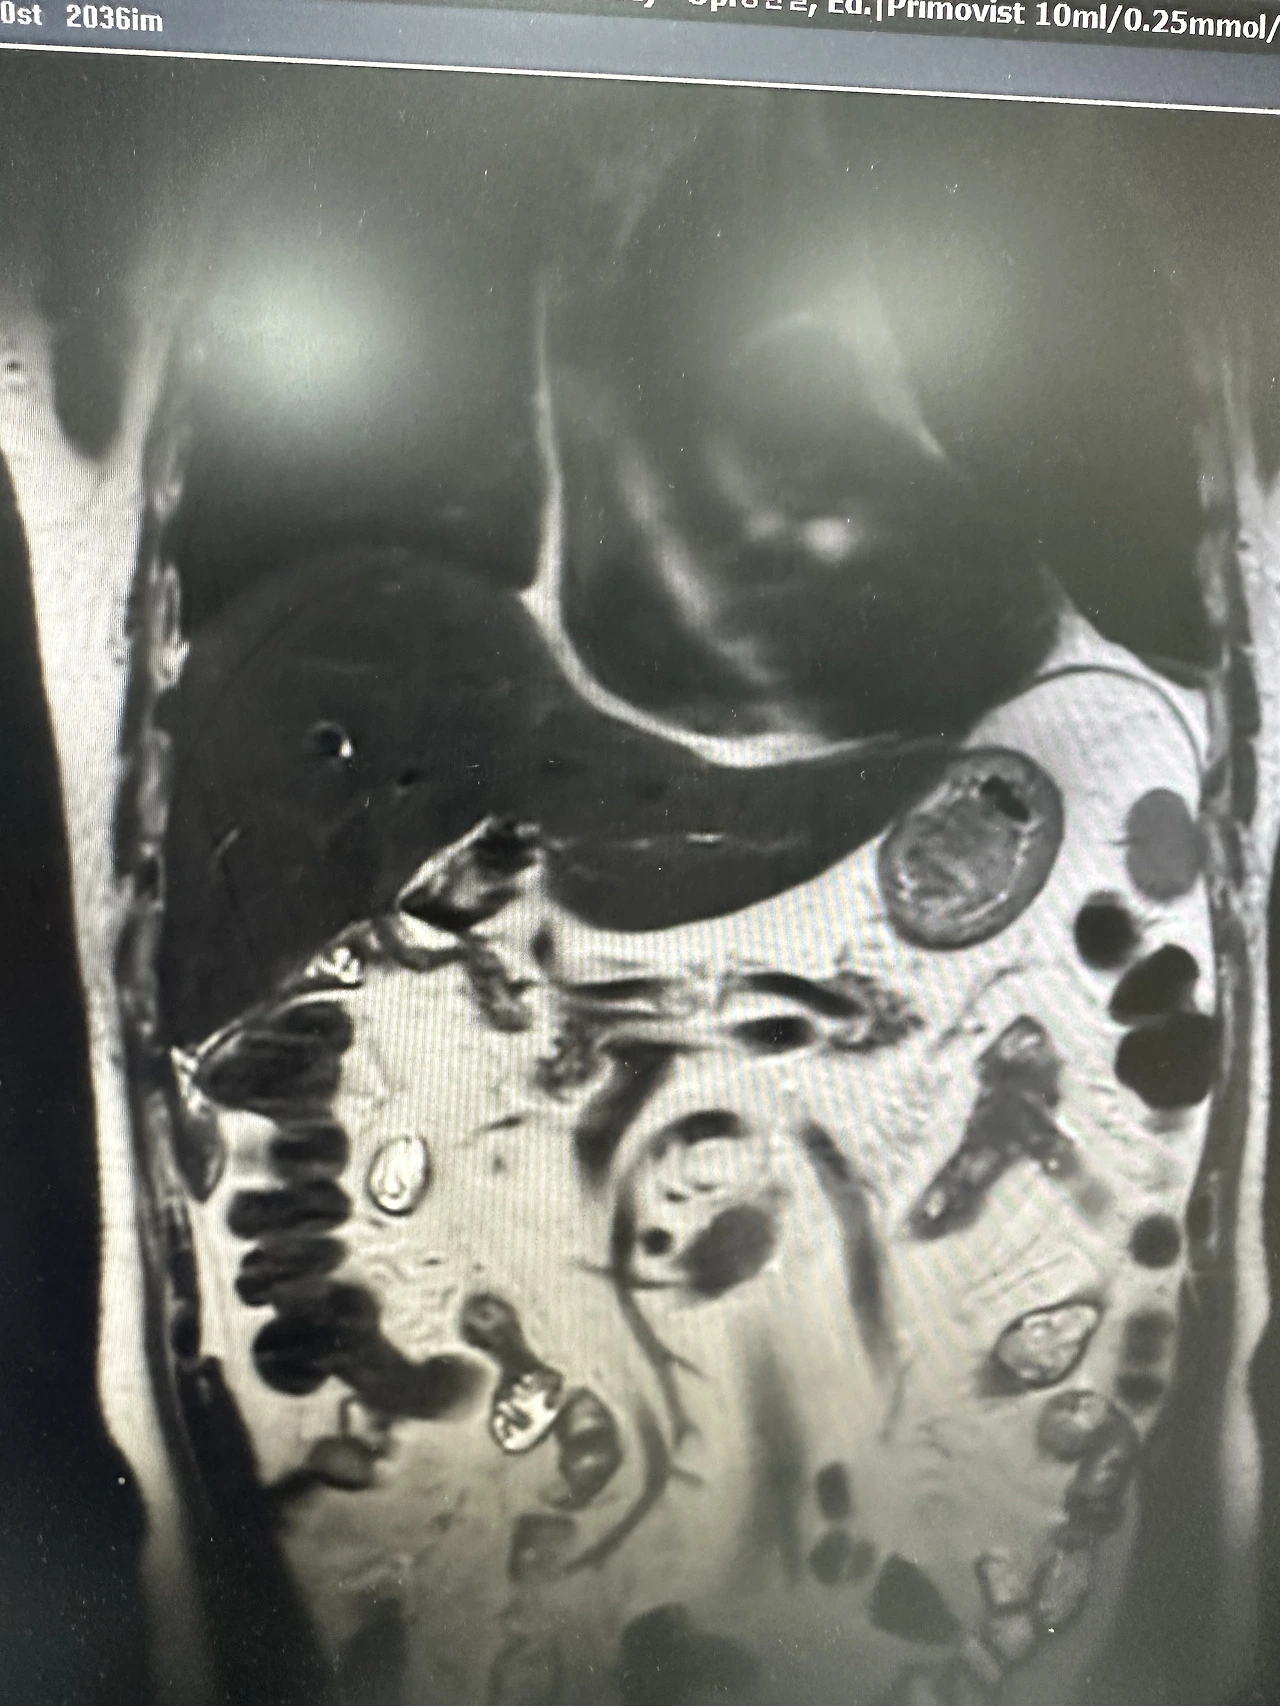

stone이나 cancer가 막고 있으려니 생각했었다. IHD는 보여도 CBD가 안 보였으니까. 그런데 lab과 환자의 반응을 보면 그렇게 나빠 보이지 않았다.

bile duct stricture인 이분은 아무리 케뉼레이션을 하고 가이드를 넣으려 해도 들어가지 않았다. 조영제를 넣어도 담관은 보이지 않았다. 과거에 담낭절제술을 했다는 것을 알고 있었지만 클립이 보이거나 수술 흔적은 보이지 않았다. 시절이 시절이니 만큼 실로 봉합부위를 손수 꿰맨 건 아니었을까 하고 교수님과 이야기도 해보았다. 만약 총담관이 막힌 채로 수술이 끝났다면 이분은 살아서 볼 수도 없었을 테니까.

duodenal fistula가 있어서 어딘가로 나오는 게 아닐까? 아니면 수술을 하면서 어딘가에 통로를 만들어 놓은 걸까? 환자의 과거력엔 담낭절제술만 적혀 있었다. 보호자가 뒤늦게 오고 나서야 그 이유를 어렴풋이 짐작할 수 있었다.